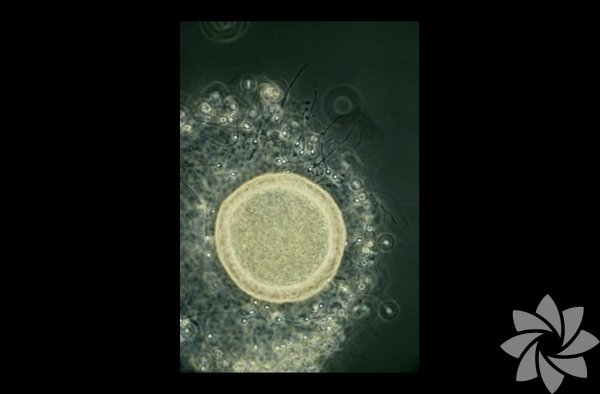

Spermler yumurta hücresinin etrafını sarmışlar!

2 / 30